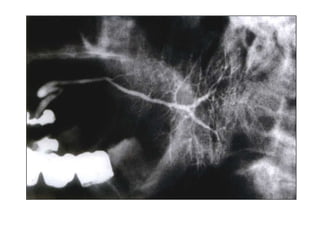

SIALOGRAPHY

It is the radiographic evaluation of the ductal tree of

the salivary glands by means of the intraductal injection

of a radio-opaque contrast solution to delineate the

ductal pattern which will be radiographically visible.

VARIOUS RADIOGRAPHIC APPEARANCES-

Normal Salivary gland – Branched leafless tree

Parotid gland – Tree in winter

Submandibular gland – Bush in winter

Tumours – Ball in hand appearance

Sjogren’s Syndrome – Cherry Blossom / Branchless fruit-

laden tree